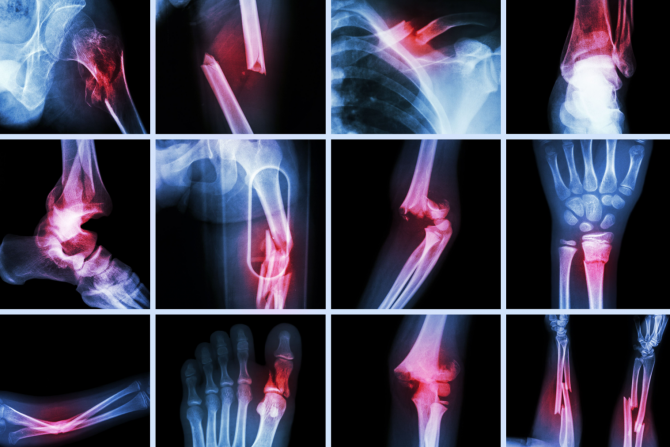

Lomovi kostiju mogu da se dese i dešavaju se svima. Stariji ljudi su više predisponirani za lomove, prvenstveno zbog smanjene gustine kostiju. Osteoporoza planetarno muči veliki broj osoba, a strah koji ovi pacijenti imaju od padova lomova je potpuno opravdan.